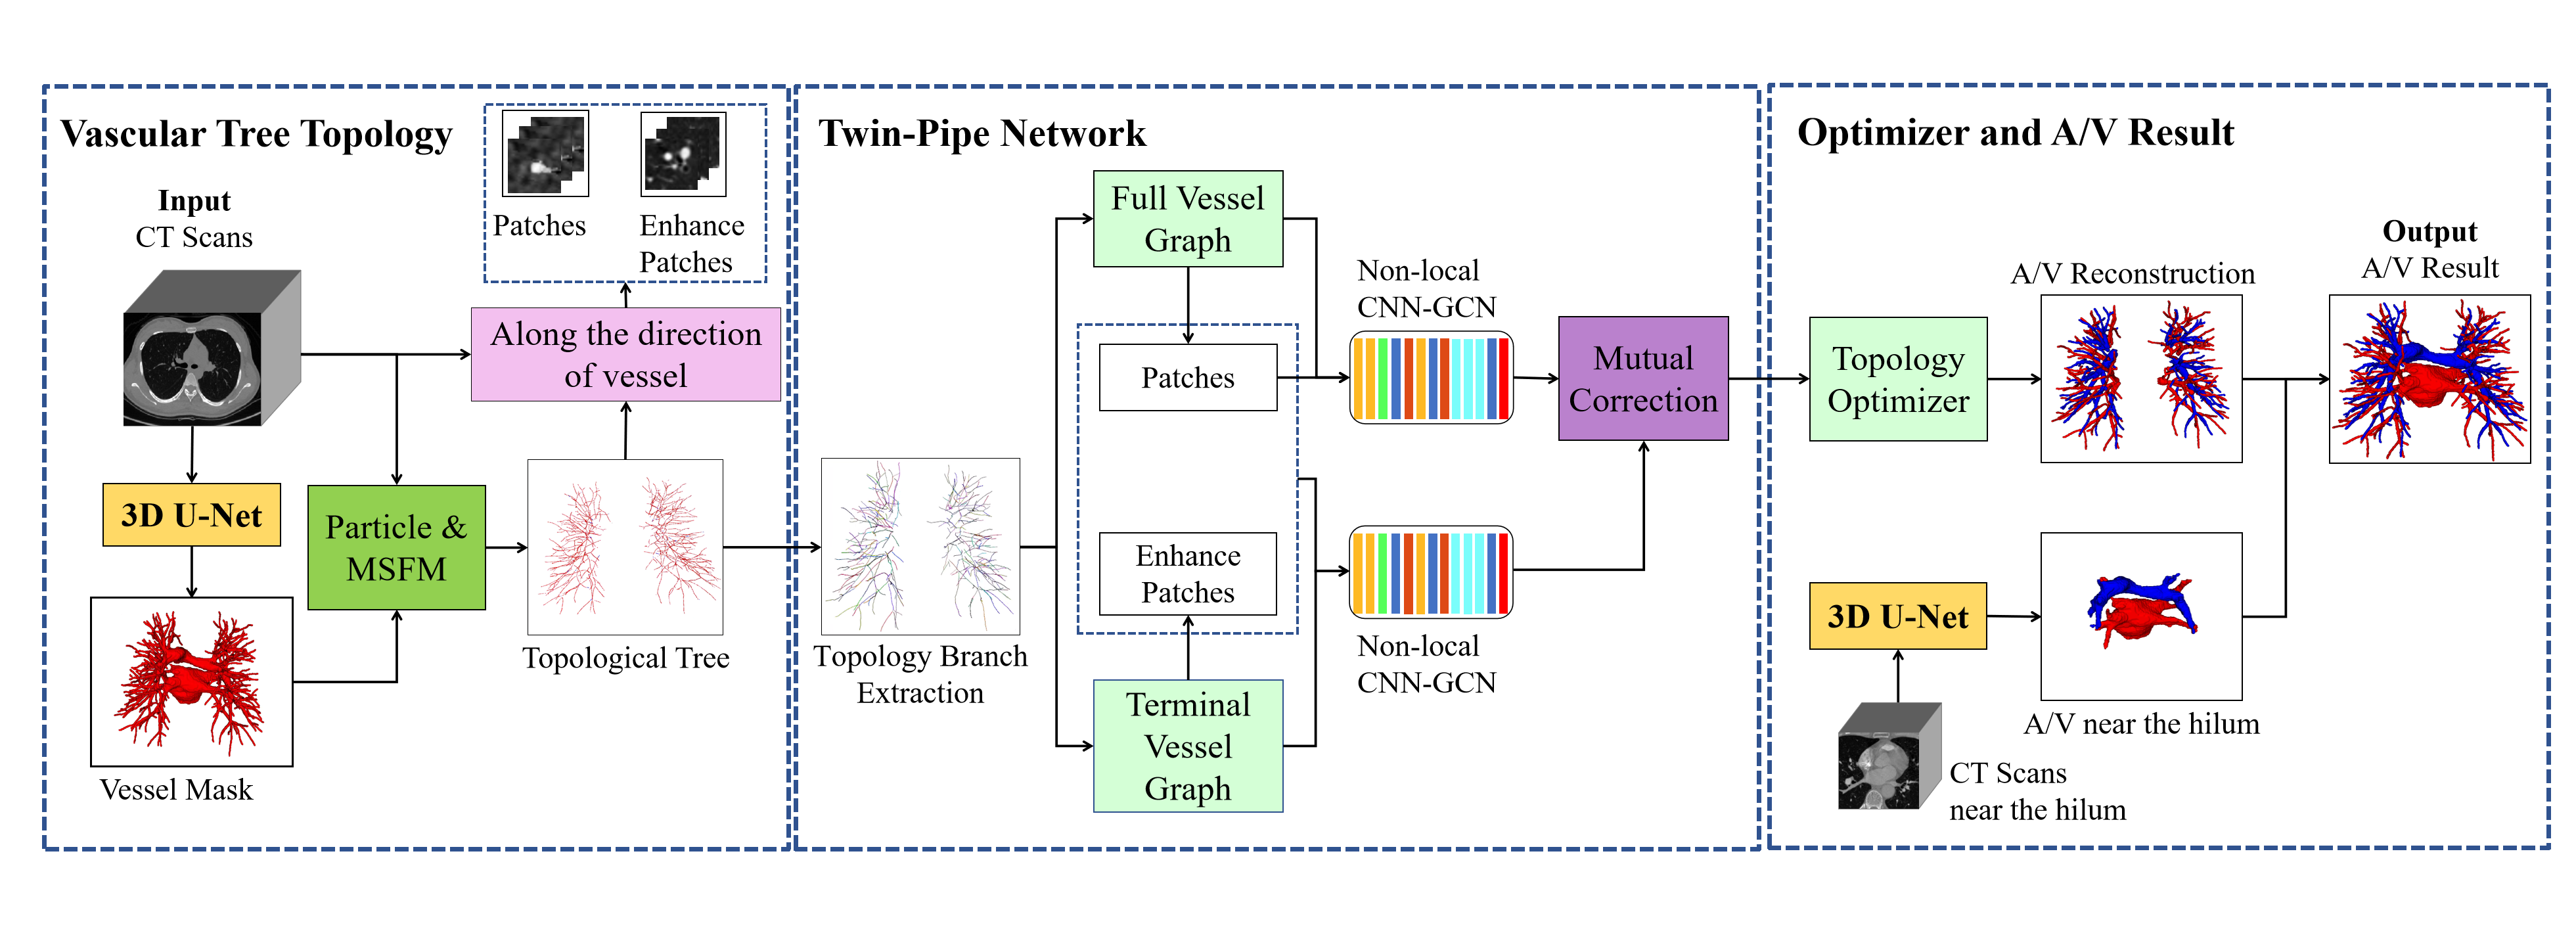

The overall framework of pulmonary A/V separation method in this paper is shown in Fig. 3, including vascular tree topology extraction, preliminary classification of Twin-Pipe network and topology optimizer refined classification pulmonary A/V results.

In the vascular tree topology extraction module, the vessels and the vessels near the hilum of the lung are segmented from thoracic CT images respectively, and a full vascular tree can be obtained by fusing them together. Then the topology is extracted, and the distance transform is used to guide and compensate the missing points flexibly. The vascular tree is represented as a collection of particles, and the vessel particles are transformed into topological trees. In Twin-Pipe network, 3D patches are taken from each particle on the topological tree as the center, and the whole vessel segment and the terminal branch vessel are trained separately from the topological tree, and the preliminary classification results of vessel particles are obtained. Finally, in optimizer and A/V result module, topological subtrees and topological branches are extracted from the topological tree, and the branch confidence is calculated to prune the subtree. Optimization of A/V classification using topological connectivity. Then, the pulmonary A/V topology is reconstructed and the A/V near the hilum are fused to obtain the pulmonary A/V results.